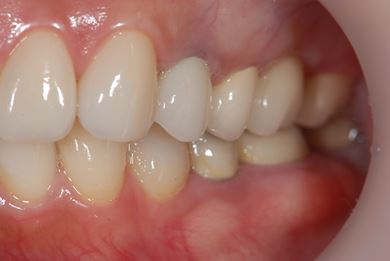

| 性別/年齢 | 女性 / 46歳 | ||||||||||||||||||||||||||||||||

| 主訴 | 上の前歯をセラミックにしたい。 | ||||||||||||||||||||||||||||||||

| 治療内容 | メタルボンドセラミックブリッジ3本(メタルボンドセラミック用土台1本)、オールセラミック5本(オールセラミック用土台4本)、オールセラミックラミネートベニア2本 | ||||||||||||||||||||||||||||||||

| 治療期間 | 9ヶ月 |